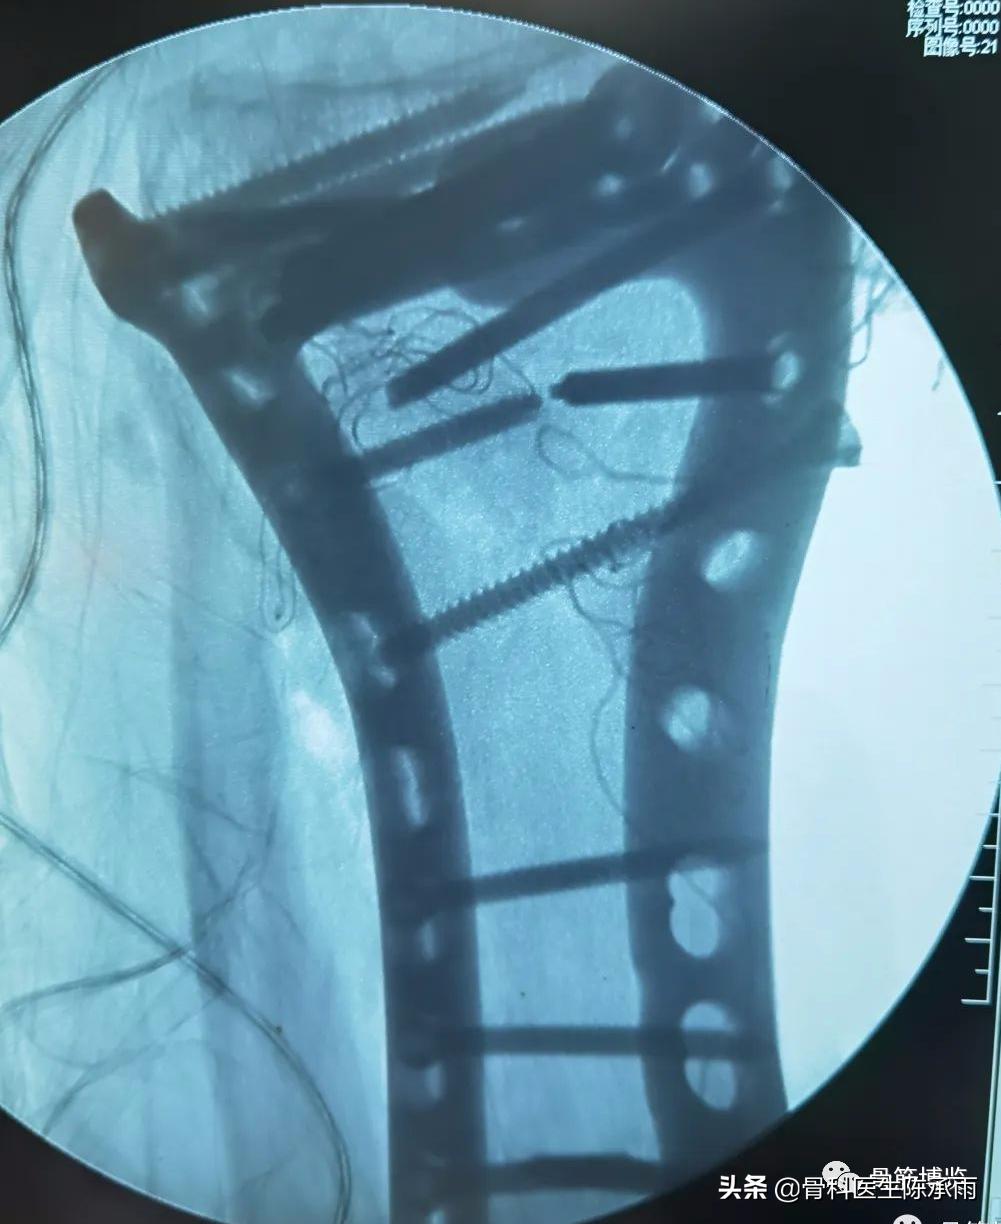

下例胫平台骨折皮肤条件差,内侧板取两端小切口置入内板固定。胫骨结节处撕脱骨折以1枚拉力螺钉固定。